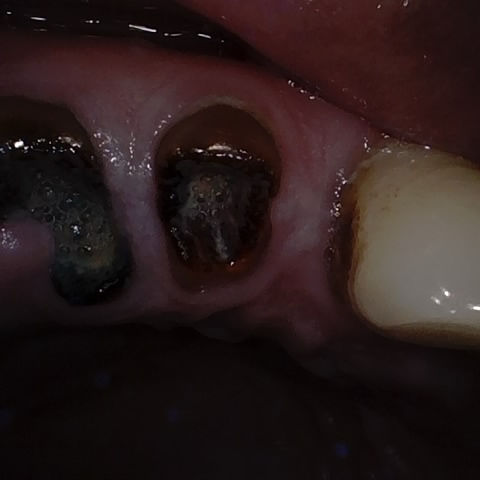

Image 1259 / 1743

NHD36692

Annotated as "Good"

Original Image Rendering Image